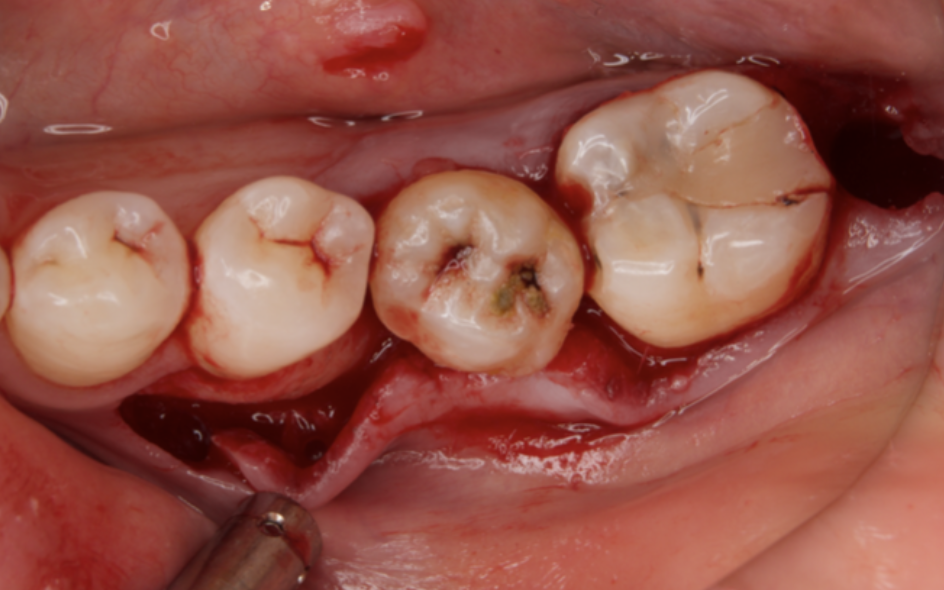

A 27-year-old female patient came to us with discomfort in the right lower jaw (Figure 1). Her primary symptoms were pain in the lower right tooth when biting and discomfort associated with not being able to chew well with the lower left single denture. The patient was married and had one young child, and previously received dental treatment in China, then had returned to Japan for childbirth and early childcare. The patient was a nonsmoker with moderate plaque control and medical history taking revealed no problems. In clinical and radiographic examinations, a root fracture was observed on tooth #46, which had been endodontic ally treated and restored with a full-cast metal crown. Periodontal probing revealed a pocket depth of 8 mm on the buccal center side of the tooth. No pain was detected with percussion and mobility of the tooth was normal. (Figure 1, Figure 2, Figure 3).

Figure 3.Preoperative intraoral findings. A metal crown was inserted at #46 and bleeding on probing during the periodontal pocket examination was noted.